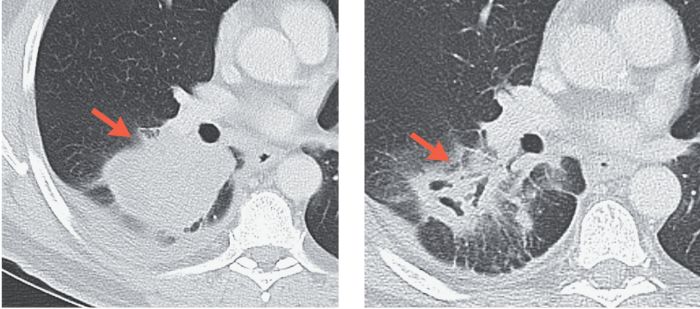

另一位病友,接受完PD-1治疗后,影像学上提示肿块变大了,但是切下来才发现原来里面绝大部分都是免疫细胞,癌细胞已经基本被消灭了!

初始影像 手术前PD-1治疗第四周